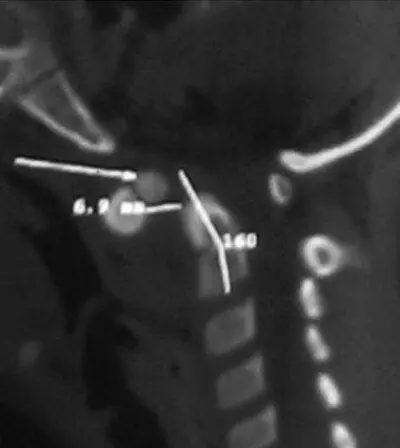

Б – КТ сагиттальная плоскость. «Зубовидная кость» величиной в 1/3 эпистрофия интерполирована в сустав Крювелье. Пространство для спинного мозга (SAC) резко сужено.

Рис.5.2 Ребенок 7 лет с костной формой кривошеи на фоне порока развития.

А, Б – 3D КТ реконструкция передняя и задняя проекция. Гипоплазия суставной поверхности и аплазия задней полудуги атланта. CI смещен вправо и вниз. Деформация частично компенсируется полупозвонком CIII справа, который вызывает наклон CII влево и блокирование латеральной нестабильности CI.